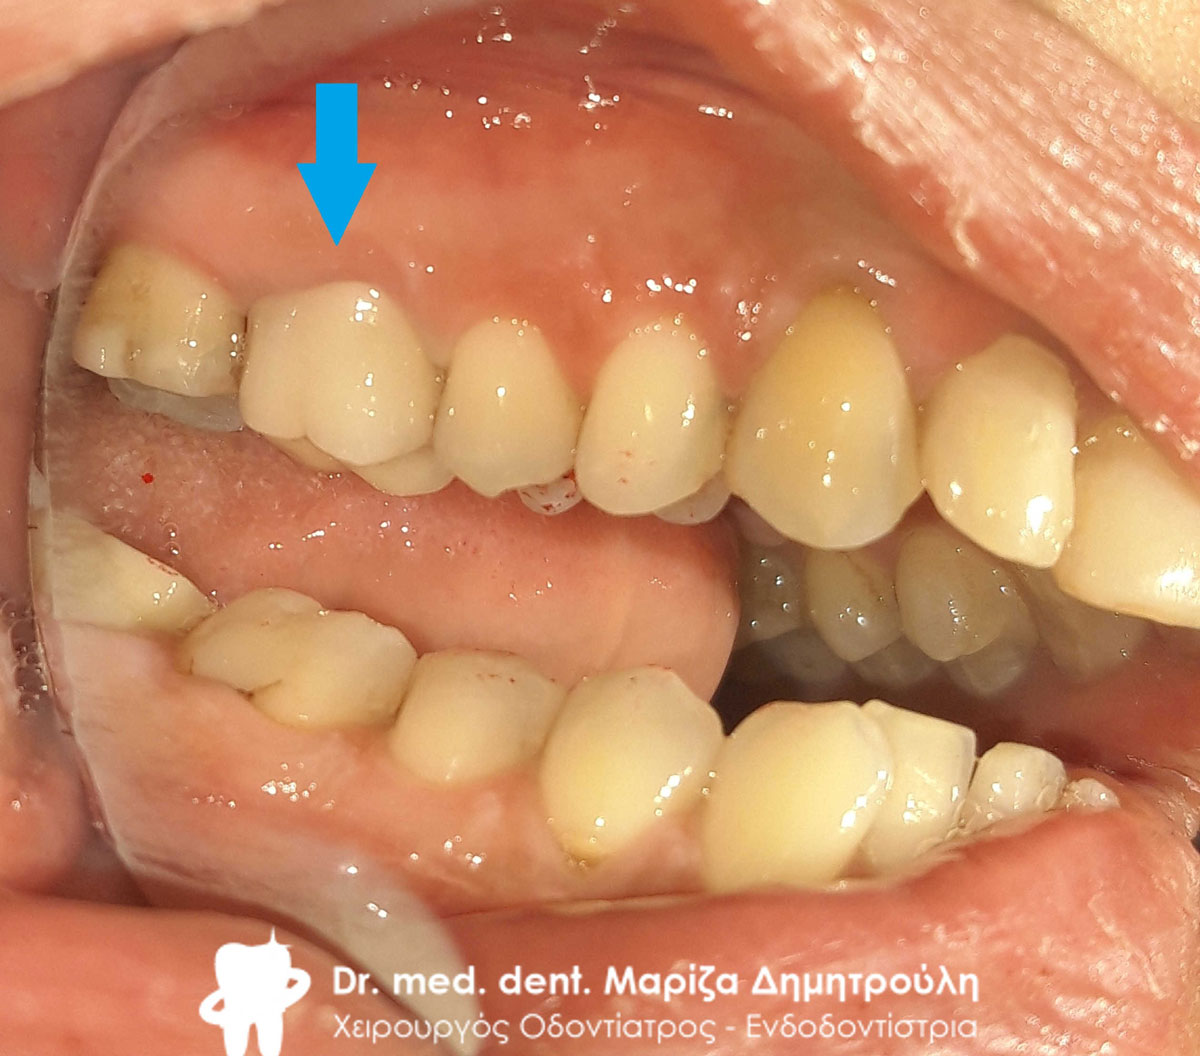

Αρχική κλινική εικόνα της αριστερής πλευράς της κάτω γνάθου

Αρχική κλινική εικόνα της αριστερής πλευράς της κάτω γνάθου

Αρχική κλινική εικόνα της αριστερής πλευράς της κάτω γνάθου

Αρχική κλινική εικόνα της αριστερής πλευράς της κάτω γνάθου

Αρχική κλινική εικόνα της αριστερής πλευράς της κάτω γνάθου